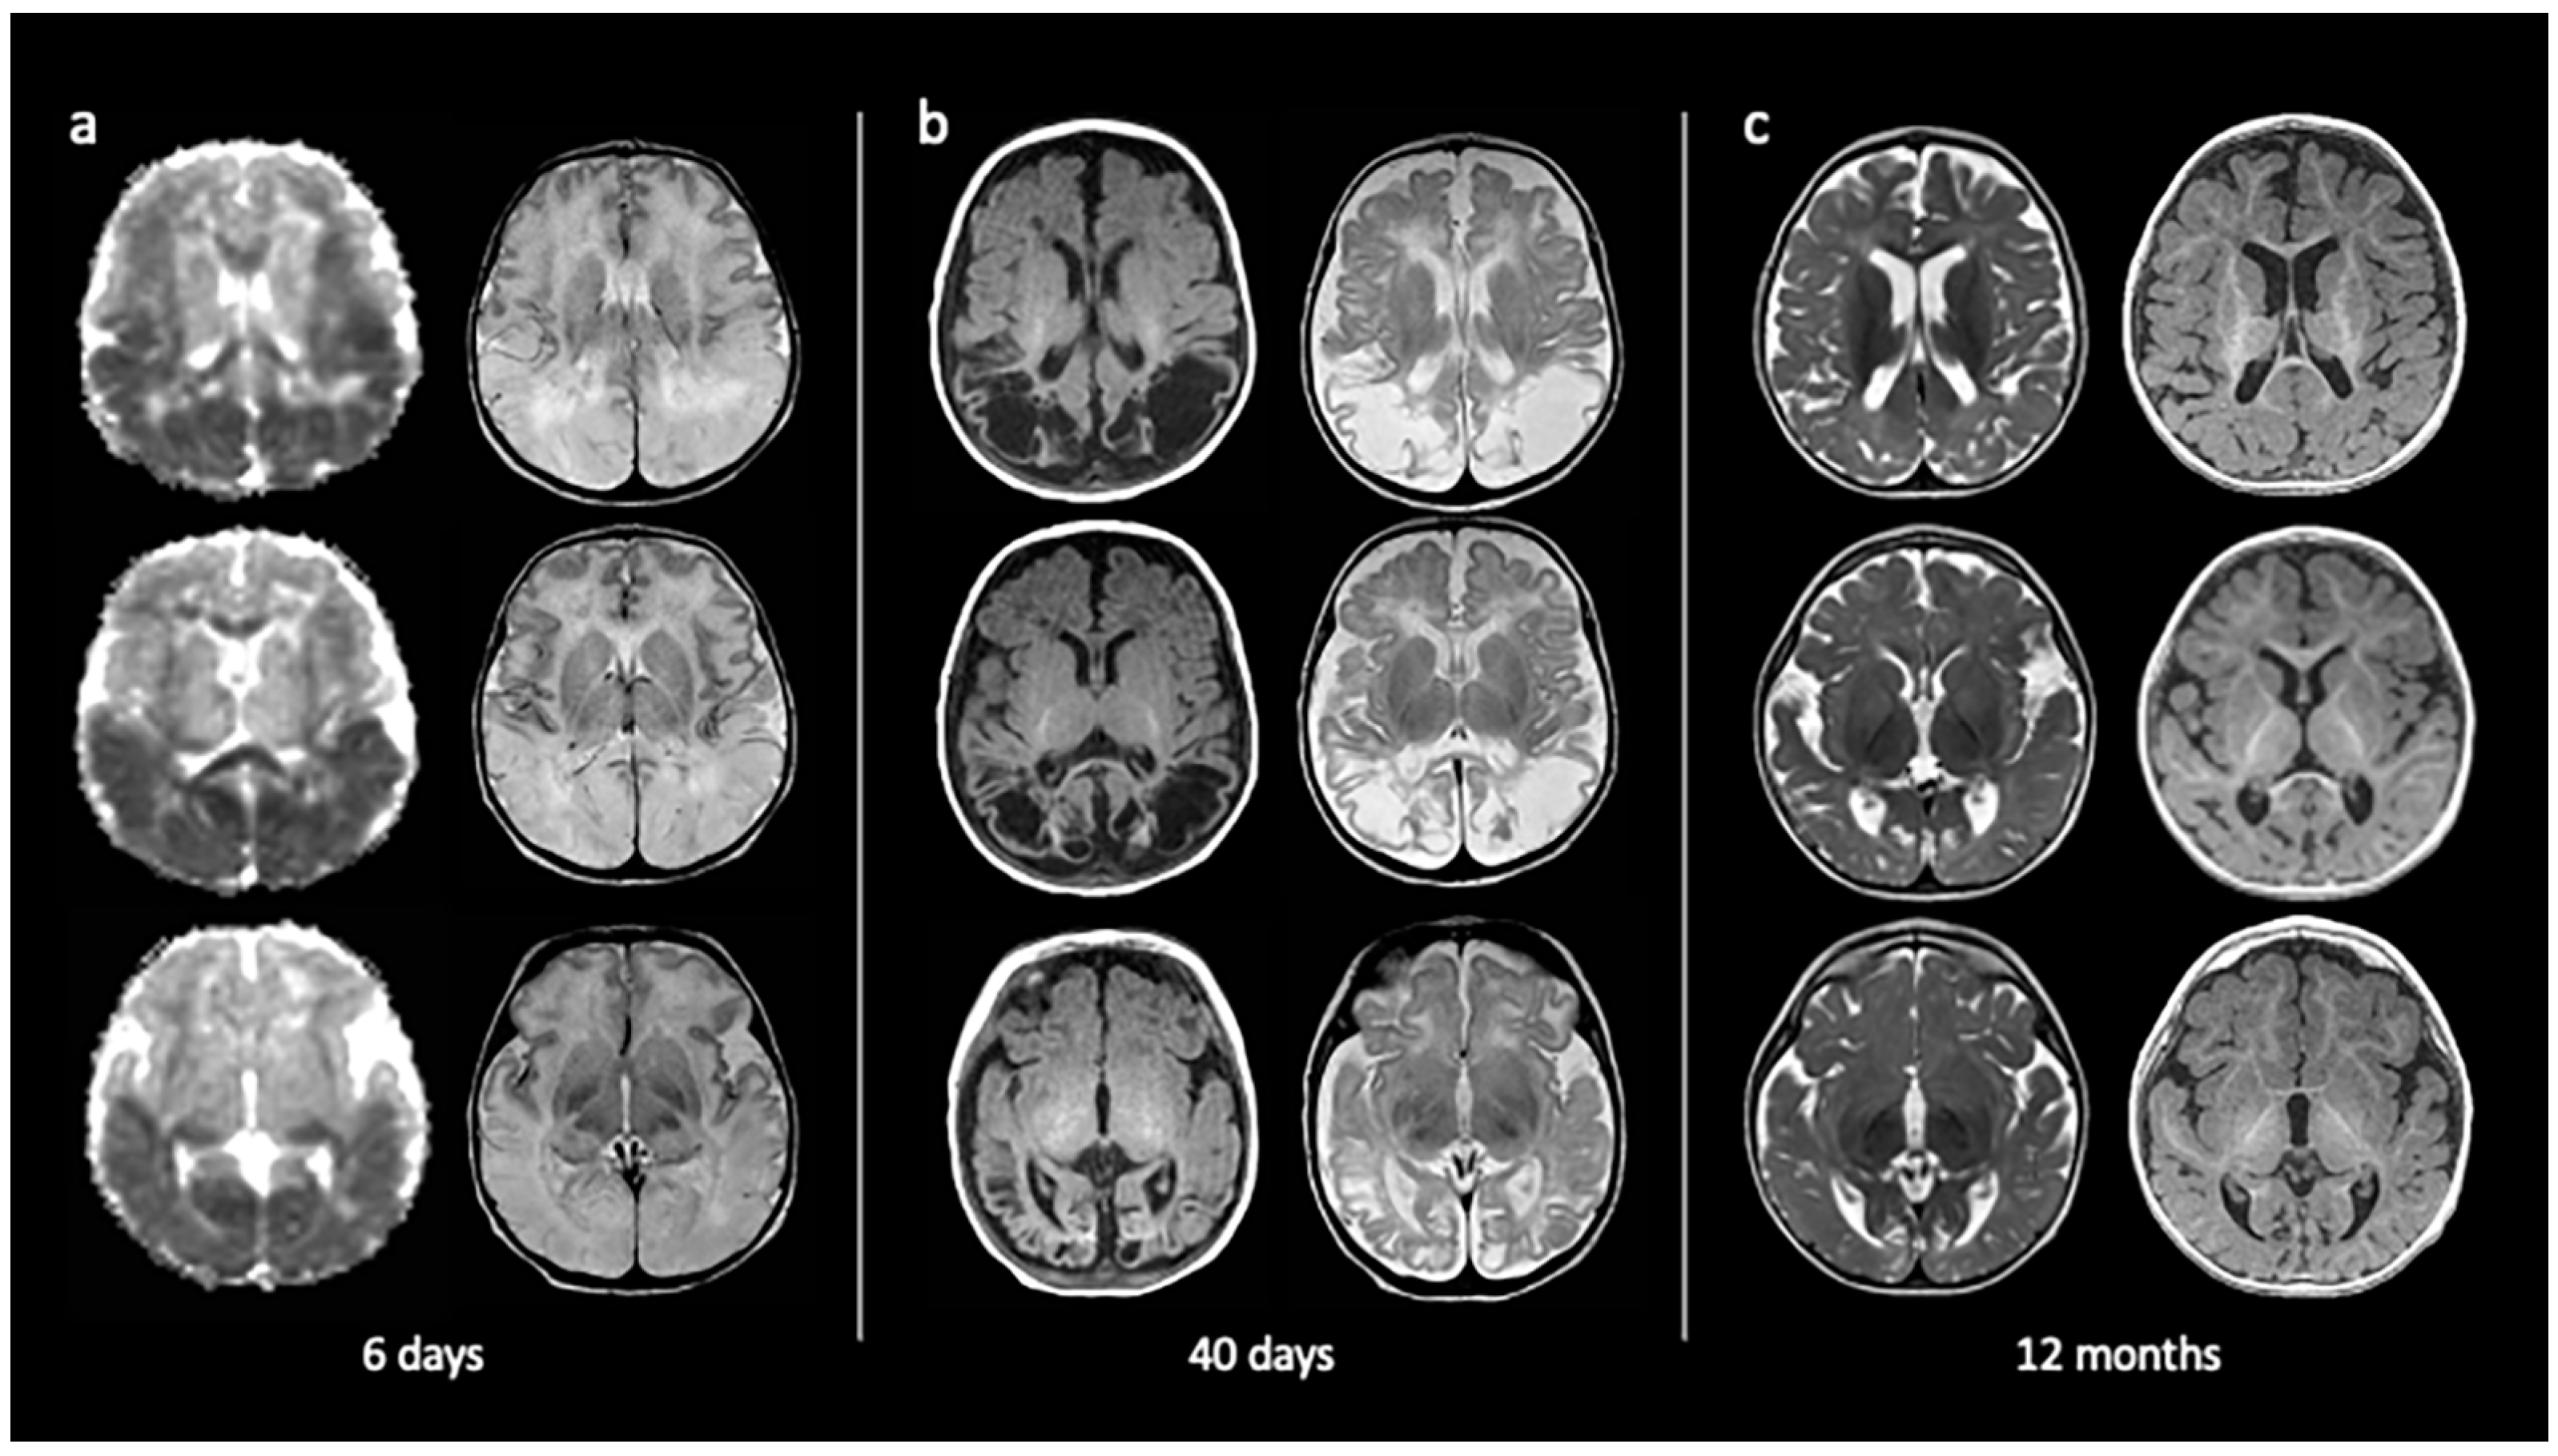

3.1.1. Neonatal Hypoglycaemia

- Alkalay, A.L.; Flores-Sarnat, L.; Sarnat, H.B.; Moser, F.G.; Simmons, C.F. Brain Imaging Findings in Neonatal Hypoglycemia: Case Report and Review of 23 Cases. Clin. Pediatr. 2005, 44, 783–790. [Google Scholar] [CrossRef] [PubMed]

- Burns, C.M.; Rutherford, M.A.; Boardman, J.P.; Cowan, F.M. Patterns of Cerebral Injury and Neurodevelopmental Outcomes After Symptomatic Neonatal Hypoglycemia. Pediatrics 2008, 122, 65–74. [Google Scholar] [CrossRef] [PubMed]

- De Angelis, L.C.; Brigati, G.; Polleri, G.; Malova, M.; Parodi, A.; Minghetti, D.; Rossi, A.; Massirio, P.; Traggiai, C.; Maghnie, M.; et al. Neonatal Hypoglycemia and Brain Vulnerability. Front. Endocrinol. 2021, 12, 634305. [Google Scholar] [CrossRef]

- Spar, J.A.; Lewine, J.D.; Orrison, W.W. Neonatal hypoglycemia: CT and MR findings. Am. J. Neuroradiol. 1994, 15, 1477–1478. [Google Scholar]